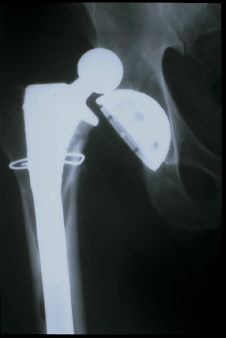

L’arthroplastie totale représente le traitement de choix pour les arthroses de hanches et de genoux. L’avantage de l’arthroplastie est qu’elle permet un soulagement de la douleur articulaire, tout en conservant la mobilité et en préservant la fonction de l’articulation.

Dans les dernières années, la qualité des matériaux s’est nettement améliorée, tant au niveau des prothèses de hanches que de genoux et la durée actuelle moyenne d’une prothèse est d’environ de dix à quinze ans.

**On parle d’hémiarthroplastie si on remplace une seule surface, et d’arthroplastie totale quand on remplace les 2 surfaces en contact. Si on voit des vis, ca veut dire que c’est une arthroplastie totale.

Les complications inhérentes à la mise en place d’une prothèse totale de hanche sont: